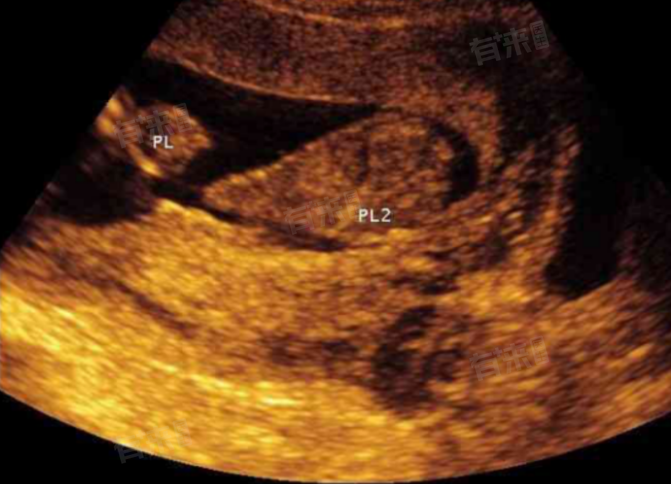

- 虽然后壁胎盘通常无需特殊处理,但孕妇仍需定期进行产检,以监测胎盘位置和胎儿的发育情况。超声检查是确定胎盘位置的主要方法,通过超声探头发出的声波,能够在屏幕上形成图像,清晰显示胎盘与子宫壁的相对位置。此外,孕妇还应关注自身症状,如出现异常阴道流血、腹痛等症状,应及时就医。

1、孕期检查:孕妇应定期进行产检,包括B超检查,以了解胎盘的位置、大小、成熟度及与胎儿的关系。通过产检,可以及时发现并处理胎盘异常,如胎盘早剥、前置胎盘等,降低分娩风险。